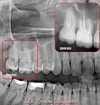

Diş hekimi